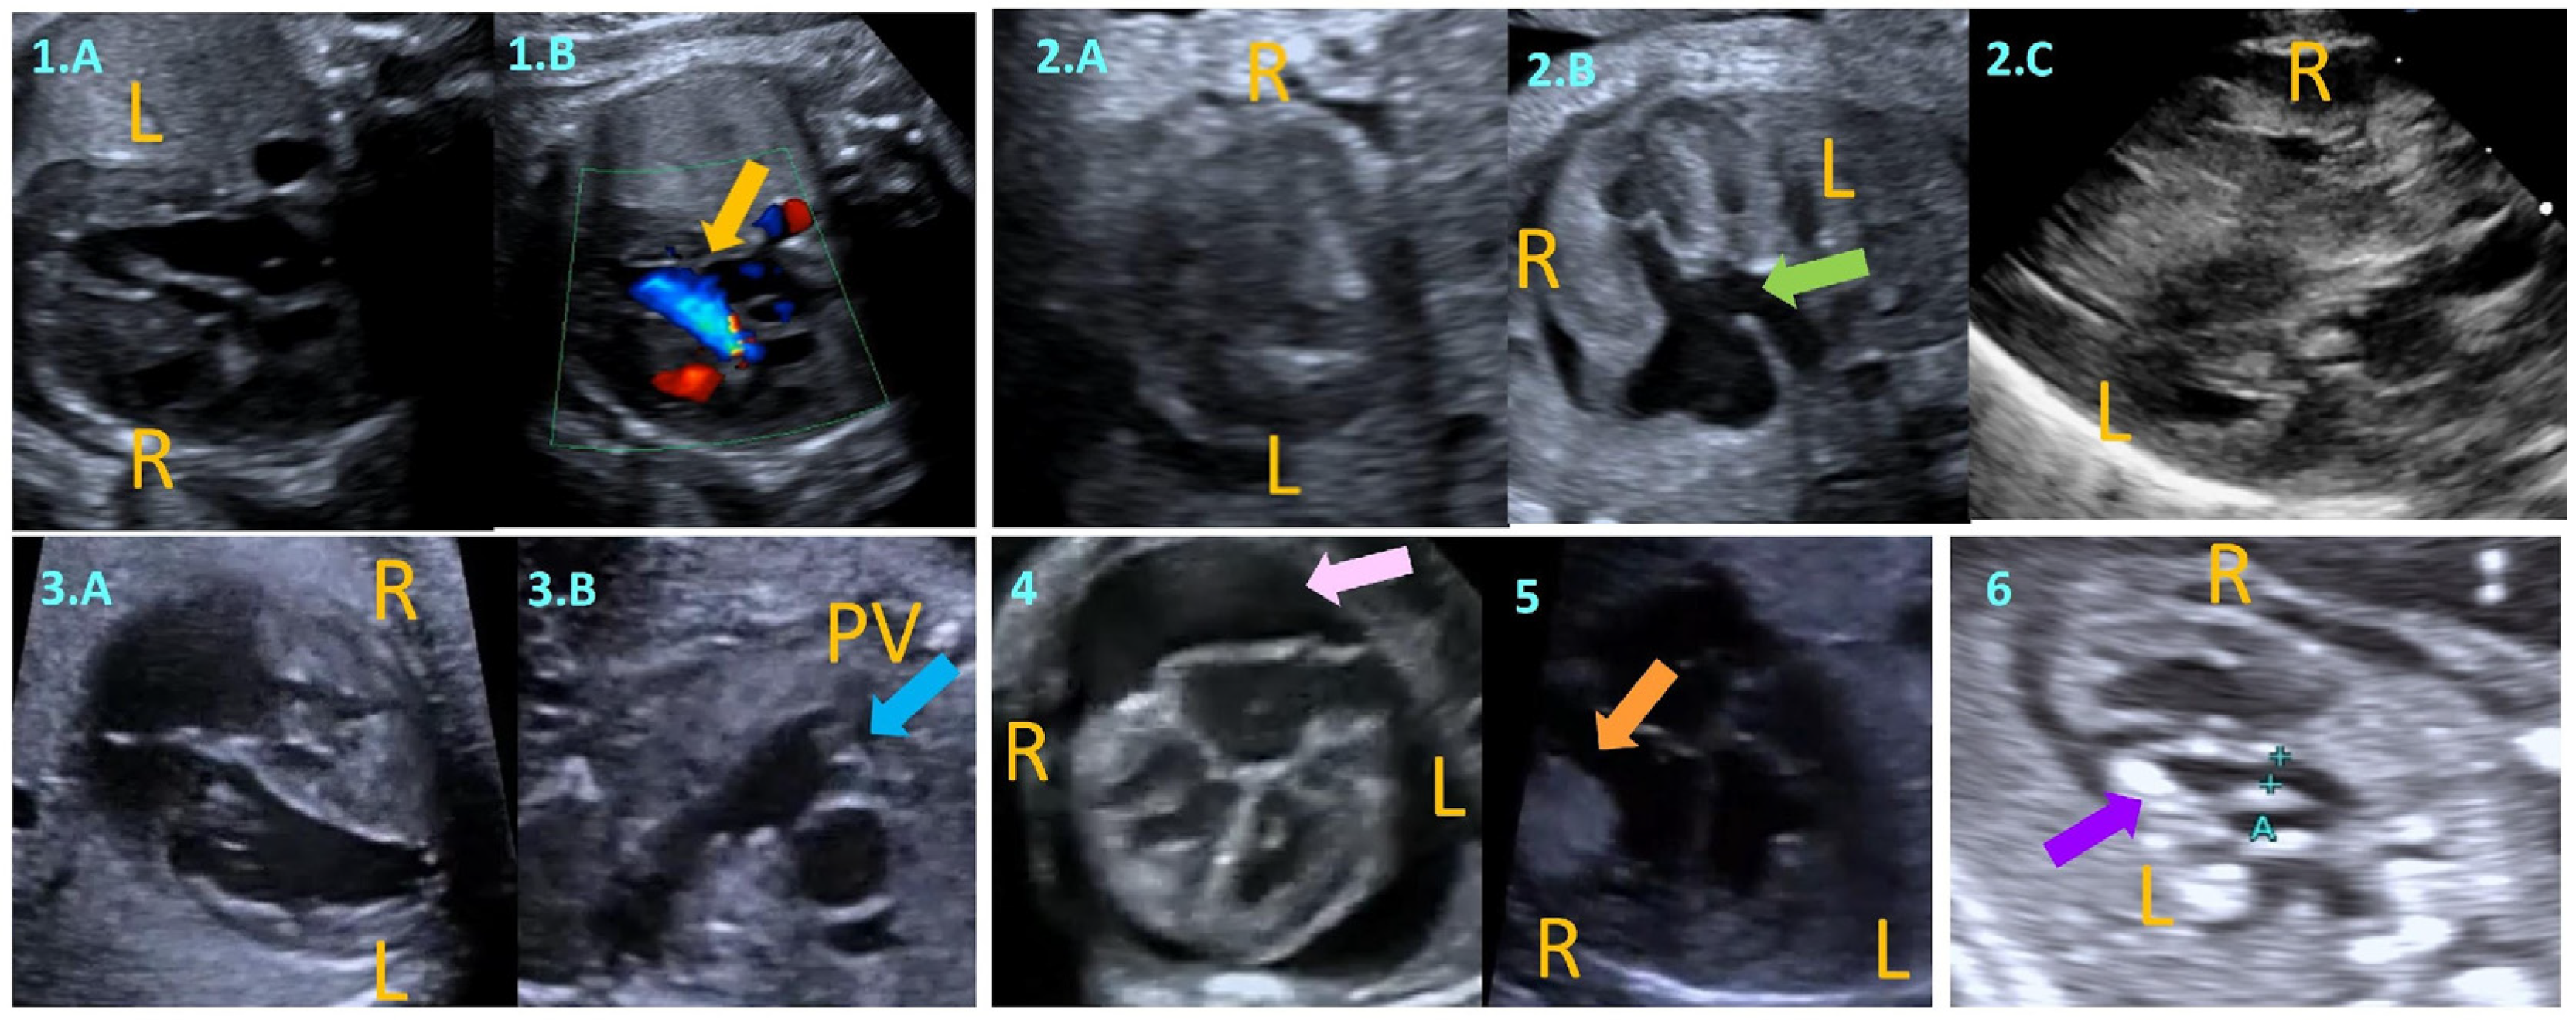

- Echocardiography